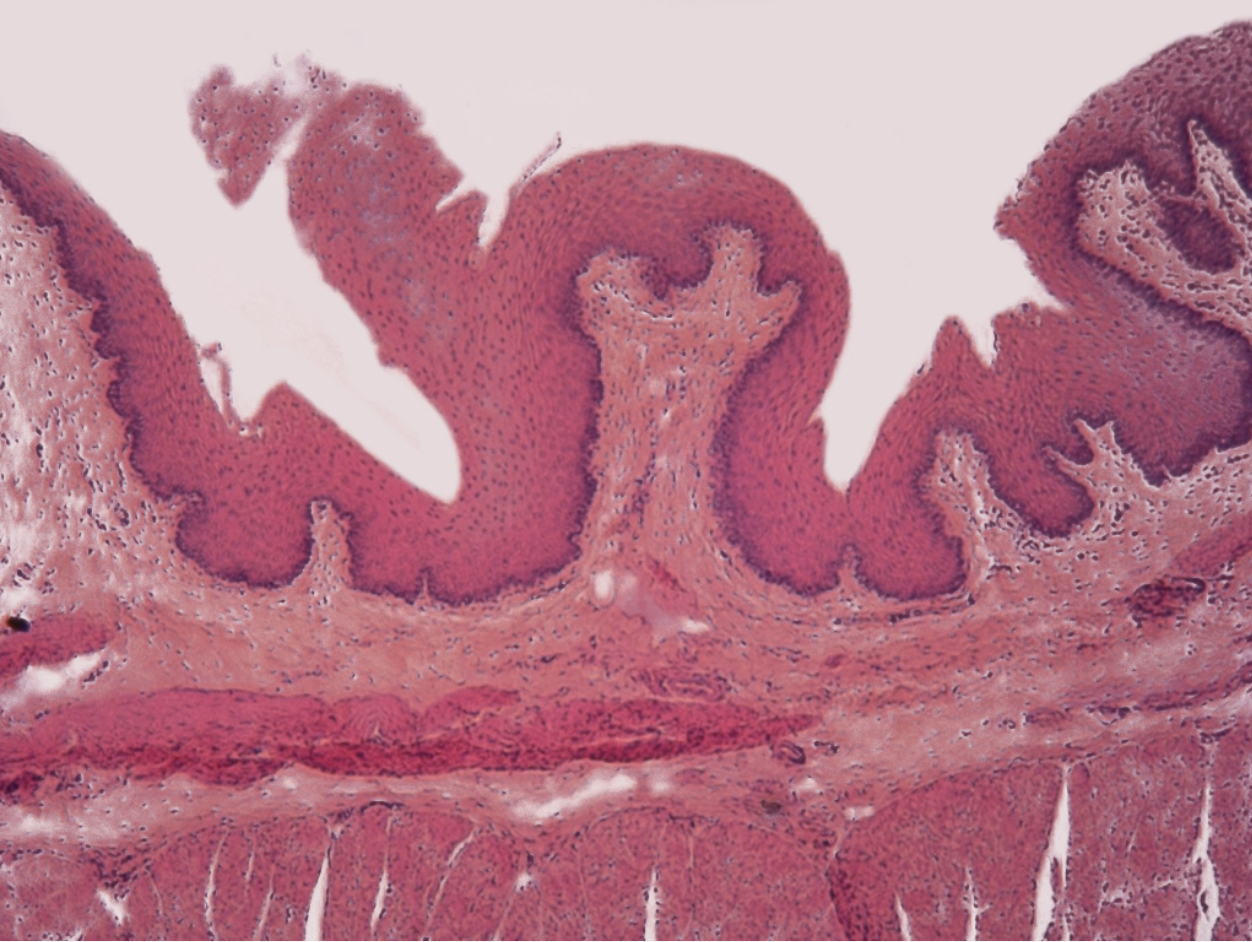

what lines the oral cavity, esophagus, and anal canal

stratified squamous epithelium (durable, protective barrier for body surfaces subjected to high friction and abrasion)

this image is of what structure?

esophagus

esophagus is made out of what cells?

stratified squamous epithelium